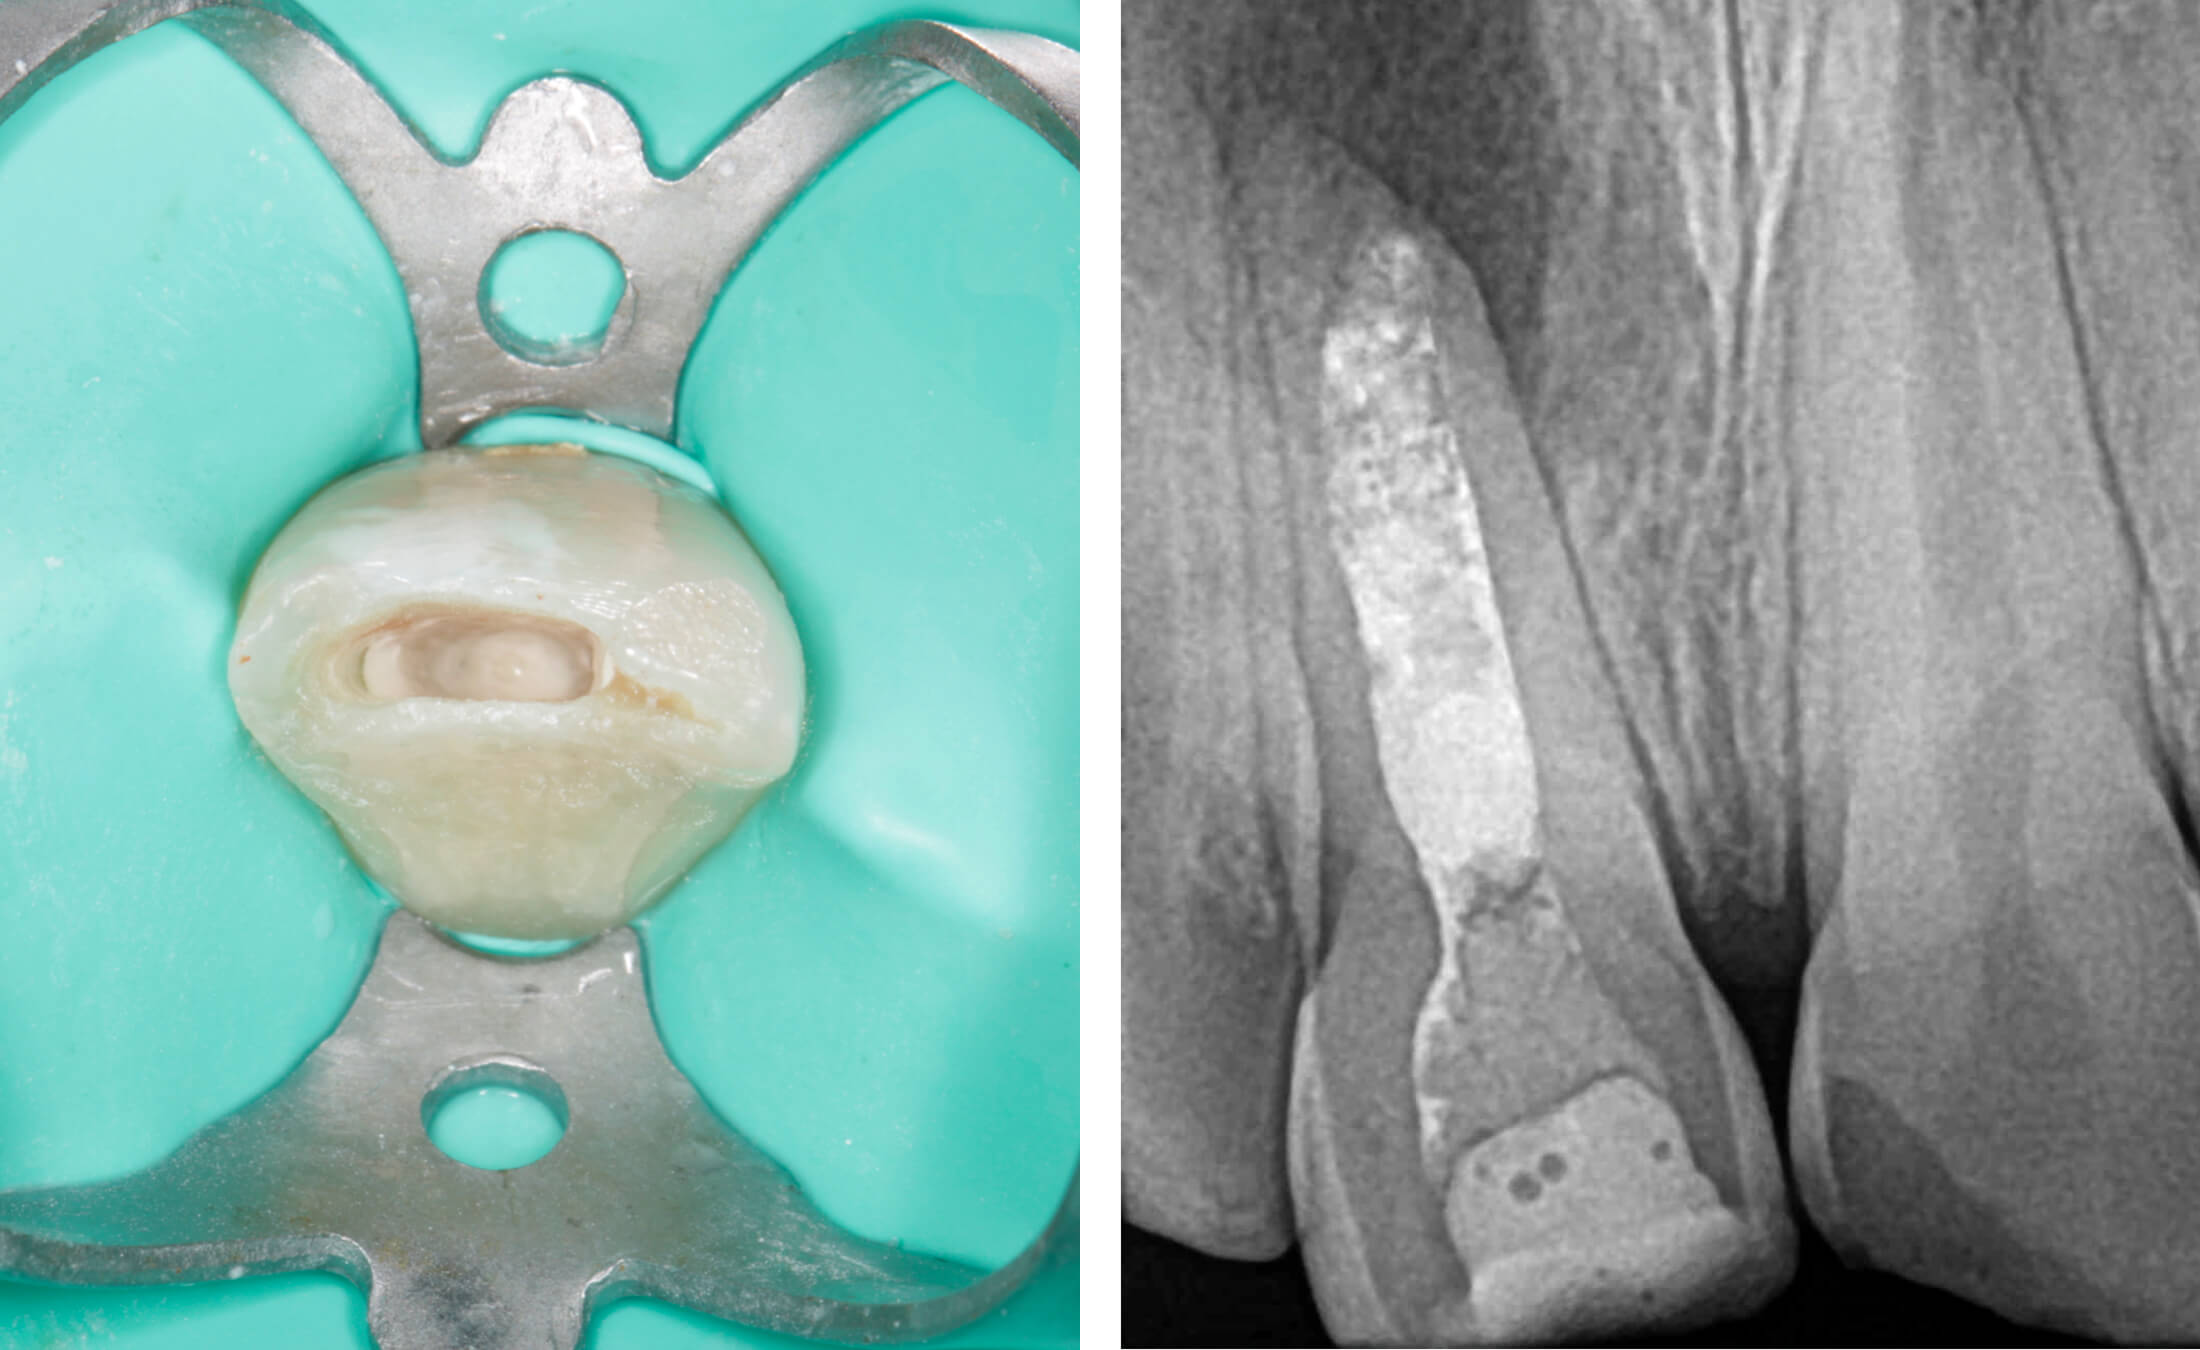

2. Зуб 11 девитален, апикальный периодонтит с обширной деструкцией костной ткани, зуб 12 витален. (Фото 2,3,4)

3. В первое посещение сформирован эндодонтический доступ, выполнена медикаментозная очистка корневого канала без применения инструментов, временная обтурация препаратом на основе гидроксида кальция сроком на 2 недели. (Фото 5,6)